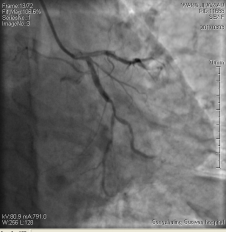

3月3日14時(shí)30分:經(jīng)右橈動(dòng)脈行冠脈造影見(jiàn):左主干未見(jiàn)明顯異常,TIMI血流3級(jí),前降支開(kāi)口正常,近中段20%狹窄,TIMI血流3級(jí);回旋支開(kāi)口正常,中遠(yuǎn)段75%狹窄,TIMI血流3級(jí)。右冠狀動(dòng)脈開(kāi)口正常,中段長(zhǎng)病變,最重99%狹窄, TIMI血流3級(jí)。

圖1 回旋支遠(yuǎn)段70%狹窄 圖2右冠脈中段99%狹窄